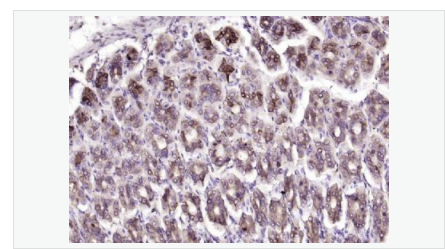

| 产品应用 | ELISA=1:5000-10000 IHC-P=1:100-500 IHC-F=1:100-500 ICC=1:100-500 IF=1:100-500 (石蜡切片需做抗原修复) not yet tested in other applications. optimal dilutions/concentrations should be determined by the end user. |